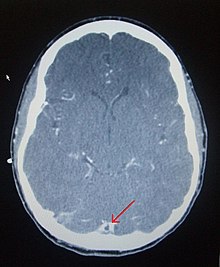

There are various neuroimaging investigations that may detect cerebral sinus thrombosis. Cerebral edema and venous infarction may be apparent on any modality, but for the detection of the thrombus itself, the most commonly used tests are computed tomography (CT) and magnetic resonance imaging (MRI), both using various types of radiocontrast to perform a venogram and visualise the veins around the brain.[4]

Computed tomography, with radiocontrast in the venous phase (CT venography or CTV), has a detection rate that in some regards exceeds that of MRI. The test involves injection into a vein (usually in the arm) of a radioopaque substance, and time is allowed for the bloodstream to carry it to the cerebral veins - at which point the scan is performed. It has a sensitivity of 75-100% (it detects 75-100% of all clots present), and a specificity of 81-100% (it would be incorrectly positive in 0-19%). In the first two weeks, the "empty delta sign" may be observed (in later stages, this sign may disappear).[11]